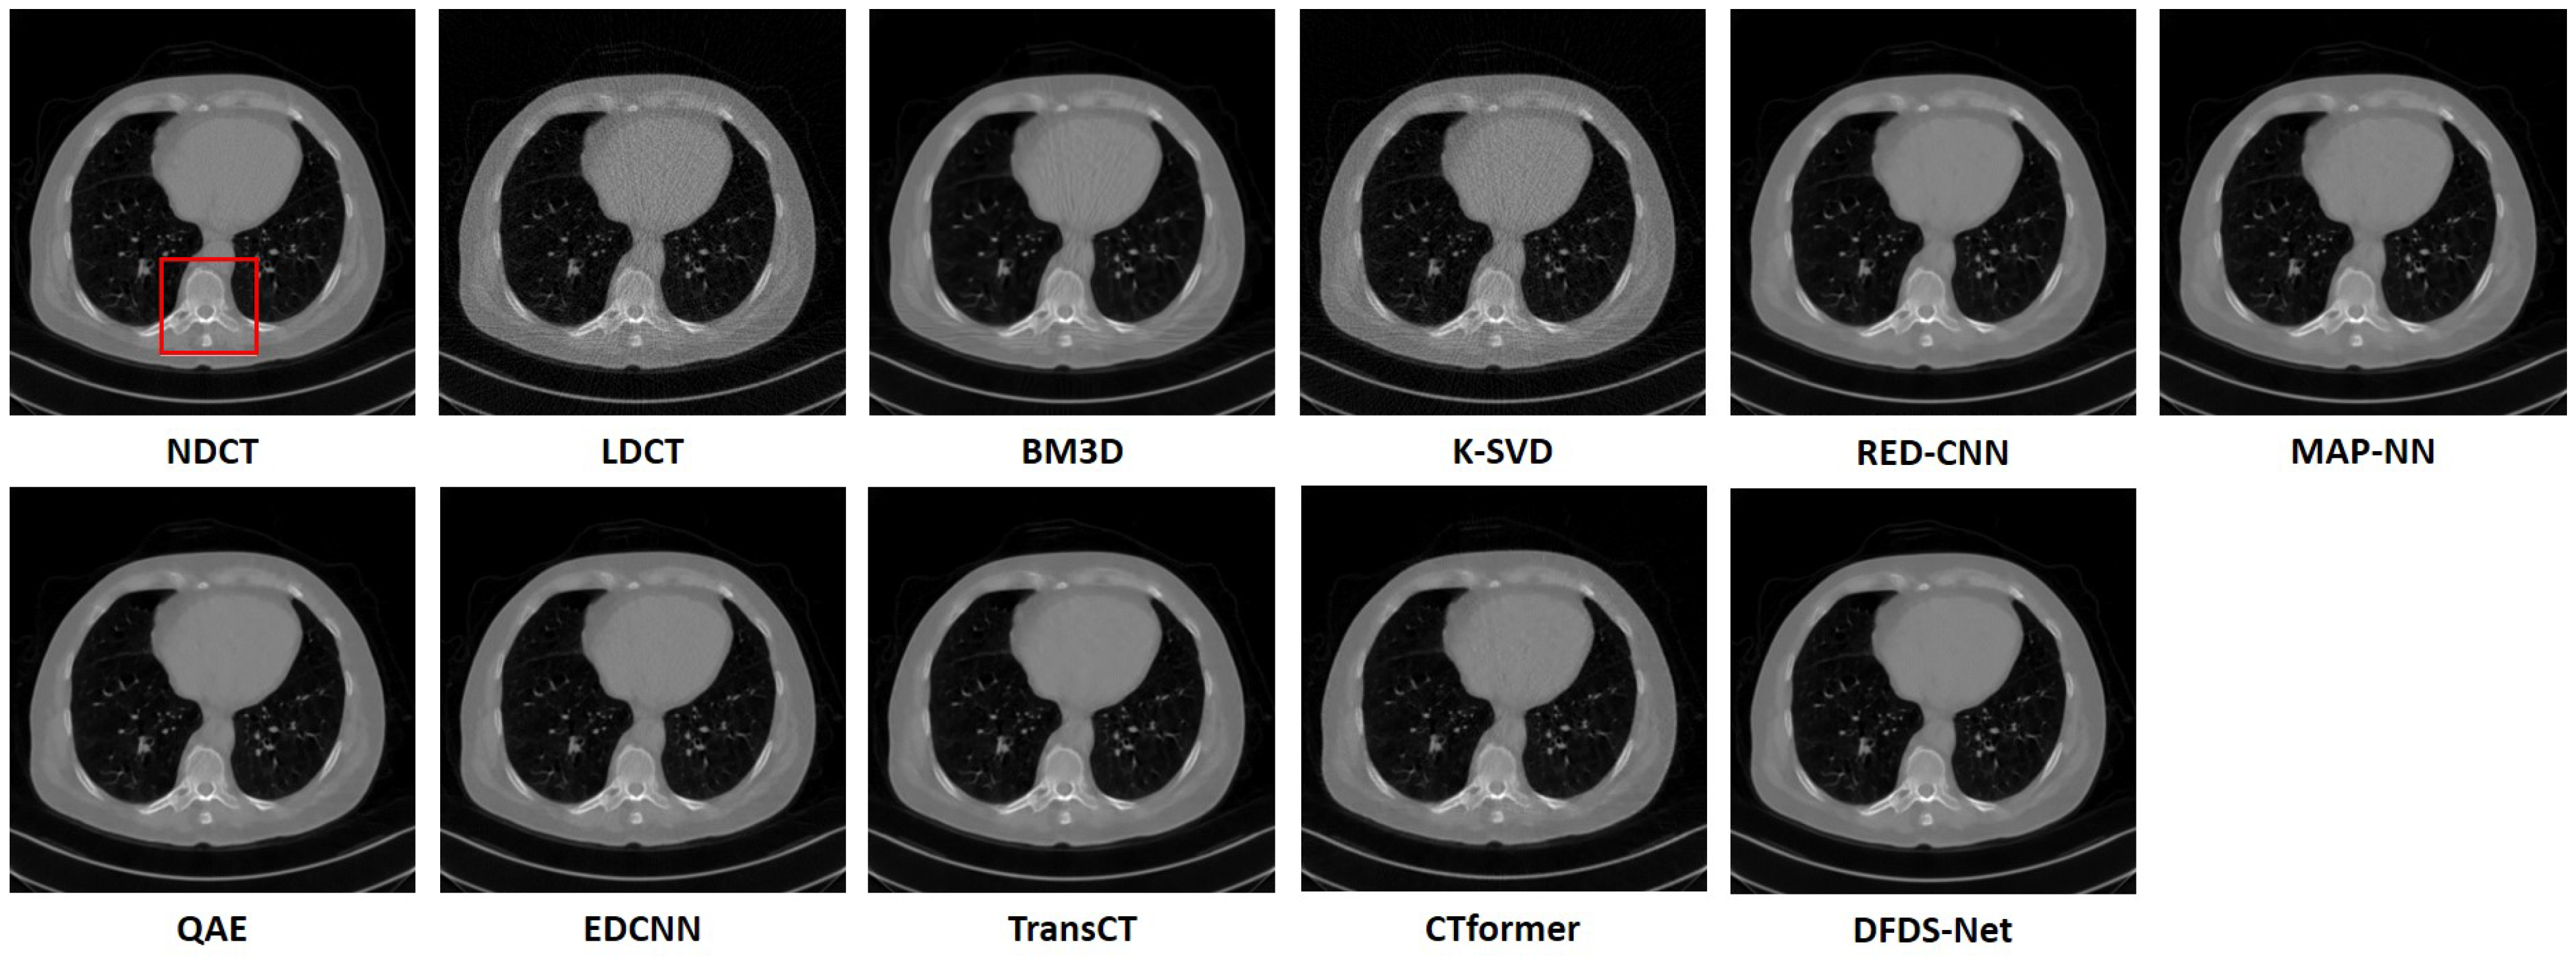

The middle section of Table 6 displays the experimental results on the chest CT dataset. Analysis of the metric values revealed that WaveletDFDS-Net achieved superior evaluation metrics, surpassing all other models. Figure 7 depicts the image restoration results of the various methods on that dataset. BM3D primarily smoothed the noise, leaving noticeable traces in the denoised images. K-SVD and CTformer exhibited limited noise reduction capabilities, with their outputs retaining significant noise residues in the whole tissue. Some other methods like RED-CNN, EDCNN, and TransCT showed similar denoising effects with higher SSIM and PSNR and lower RMSE than BM3D, K-SVD, and CTformer but tended to produce blurry images. MAP-NN and QAE demonstrated improved denoising performance and image quality. Nevertheless, WaveletDFDS-Net further enhanced the denoising efficiency and restored images with quality closest to NDCT images. Figure 8 enlarges the partial details of the region marked by the red box in Figure 7, which provides a better observation. The quantitative results corresponding to these observations are presented in the middle section of Table 7, related to Figure 7.

Figure 7. Comparison of the qualitative performance of WaveletDFDS-Net and other well-known low-dose CT denoising methods on the chest dataset. The display window is [−1000, 1000] HU.

Figure 8. The zoomed images over the region of interest (ROI) marked by the red box in Figure 7. (a) BM3D, (b) K-SVD, (c) RED-CNN, (d) MAP-NN, (e) QAE, (f) EDCNN, (g) TransCT, (h) CTformer, (i) WaveletDFDS-Net.